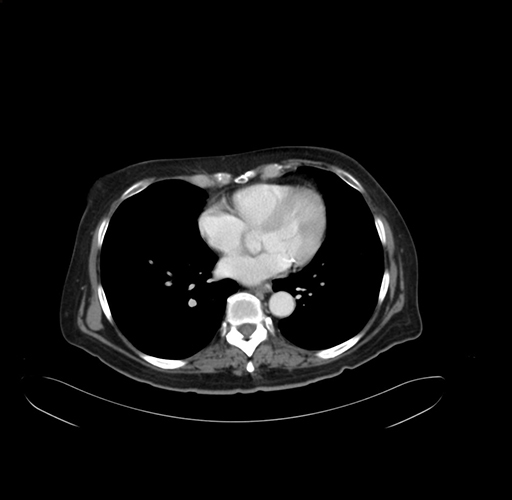

Pre-Chemo: Axial Venous

Axial Venous

Imaging analysis

Based on your CT findings, which issue(s) would give reason for "planned slowing down moment(s)" in this case?